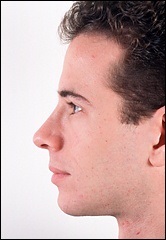

A fénykép a bal oldalon mutatja egy ember tipikus megnövekedett nazális gerinc. Ez jelentősen növeli az orrát előre. A fénykép után a művelet ugyanaz az ember nagyon jól néz ki.